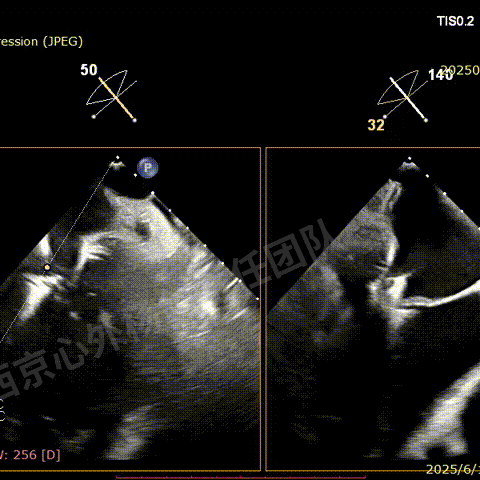

二尖瓣后叶栓系严重,前叶相对错位,反流束沿2区分布广泛,2偏3区处存在反流。

反流宽度至少23mm,因影像调整困难,考虑实际反流更宽。